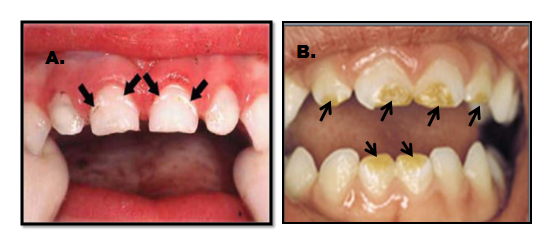

Vrlo je važno da se razlikuje karijes od razvojnog defekta. Karijes se pojavljuje kao bela mrlja na prethodno normalnoj gleđi i to pre svega uz ivicu desni. Rezvojni defekat je uglavnom na drugim površinama, gde se karijes ne javlja. (Slika 4. i 5)

Karijes kod beba brzo napreduje i razara celu površinu zuba, pa ponekada može da podseća i na razvojne defekte.(Slika 5.)